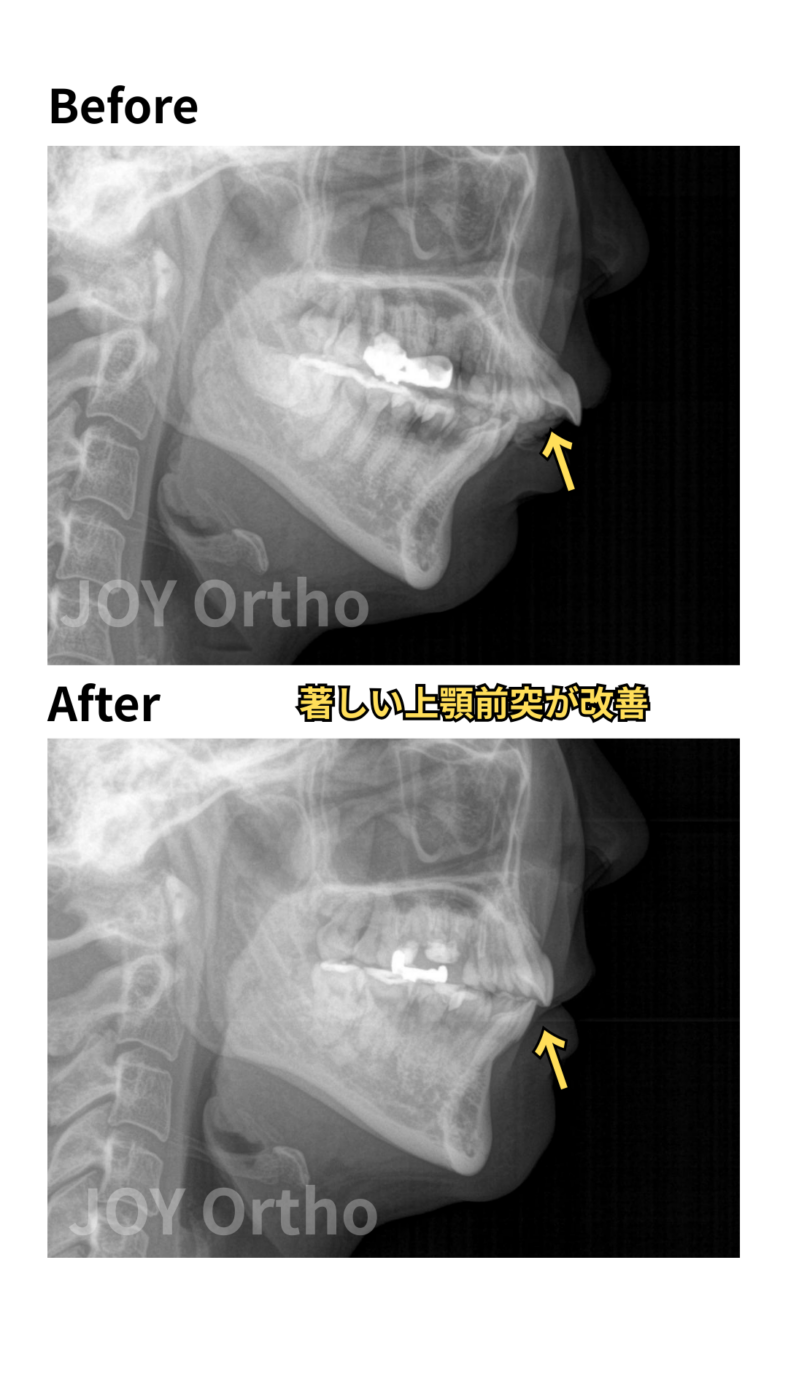

上顎前突が改善してきている。

症例8

- 主訴:上の歯が出ている、口が閉じにくい、すき間、歯並び

- 診断名:上顎前突症、開咬、下顎前歯先天欠如

- 初診時年齢:24歳

- 治療に用いた主な装置:マウスピース型カスタムメイド歯科矯正装置、部分マルチブラケット装置、歯科矯正用アンカースクリュー

- 抜歯部位:上顎左右4番、下顎左右7番

- 動的治療期間・通院回数:10ヵ月(治療中)・約7回

- 治療費概算:約120万円(税込、検査・診断料+矯正治療費+大臼歯加算+スクリュー費)+毎回の処置料3,300~5,500円(税込)

- リスクと副作用: 歯根吸収の可能性がある。大臼歯移動のため、通常より治療期間が延長する可能性が高い。